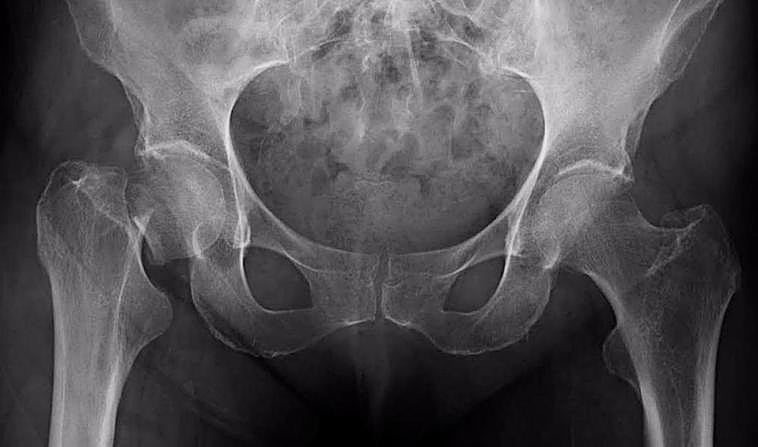

El motivo por el que es importante prevenir las fracturas de cadera

el tratamiento posterior a la fractura sigue siendo inadecuado en muchos países